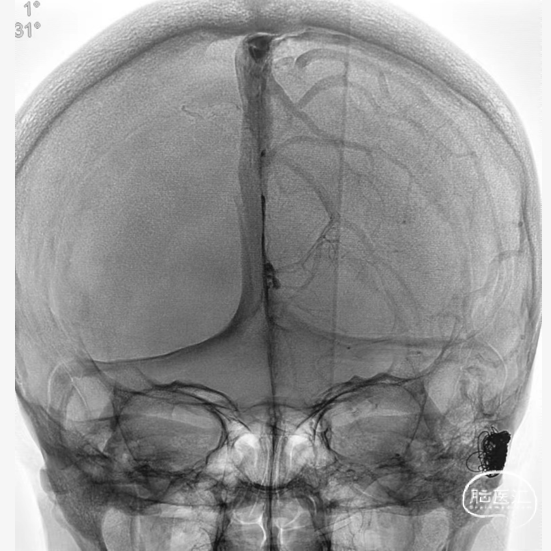

术前影像学检查

➤DSA